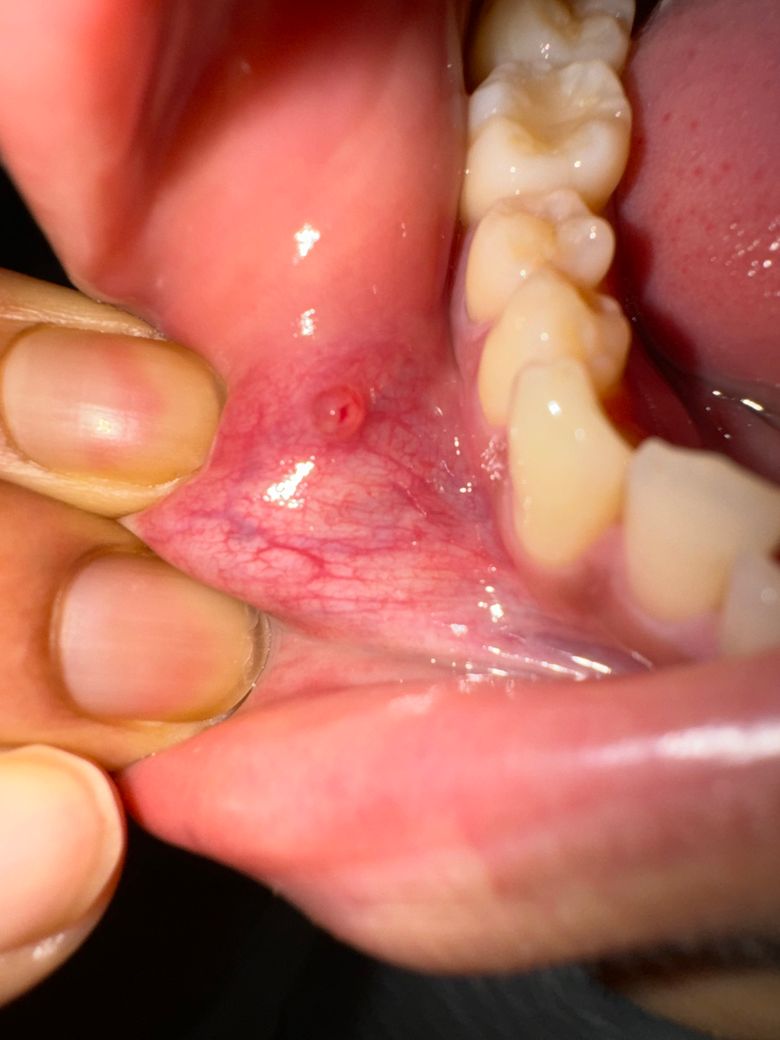

입 안에 물집이 생겼는데 안사라져요.

한 열흘정도 전에 좀 피곤하고 스트레스받는 일이 있었어서 그런지 입 안에 물집이 생겼었는데요. 알보칠 바르니까 그 때는 점막이 하얀색이였는데 그게 벗겨지고 물집이 생겼어요. 좀 더 커진느낌인데 구강암같은거일 수 있나요?

구강암일 가능성은 낮으며, 구내염이 생긴 것으로 보입니다. 알보칠은 구강점막에 자극감이 쎄기에 현재 해당부위 소독을 위해 헥사메딘 가글액으로 가글하여 관리하고, 구내염에 바르는 연고 및 점막재생을 돕는 비타민 섭취를 권합니다.

사진으로 봤을 경우에는 점액종이라고 불리우는 증상일 수 있습니다. 점액종은 점막 안에 조지기 튕기면서 만들어지게 됩니다.

점막이 외부 자극에 강하게 자극이 되었을 경우 생길 수 있기 때문에 치아에 가해지는 힘을 줄여보는 것이 좋습니다. 또한 치과에서 가볍게 제거할 수도 있기 때문에 자세한 확인을 위해서 치과에서 진료를 받아보는 것을 권유 드립니다.

입술이 치아에 씹혀서 생긴 물집으로 터트리시면되고 개속해서 반복적으로 생기면 치과에 가셔서 마취후에 레이저같은걸로 제거를 하시는게 좋습니다 .

단순 구내염으로 판단됩니다. 시간이 지나면 자연스럽게 없어질 것 같지만 계속 있다면 치과 가보시면 됩니다.